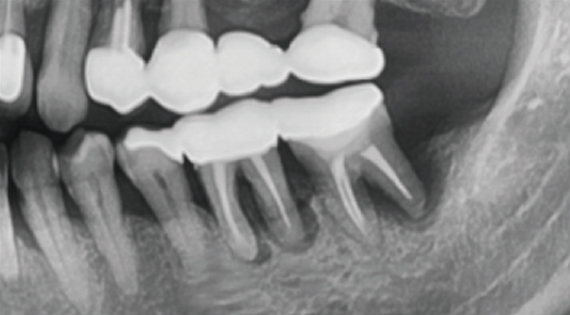

After tooth extraction, implant placement is possible

by minimizing bone graft.